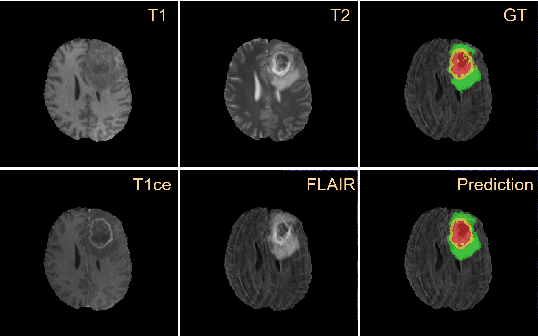

Abstract:A glioma is a malignant brain tumor that seriously affects cognitive functions and lowers patients' life quality. Segmentation of brain glioma is challenging because of interclass ambiguities in tumor regions. Recently, deep learning approaches have achieved outstanding performance in the automatic segmentation of brain glioma. However, existing algorithms fail to exploit channel-wise feature interdependence to select semantic attributes for glioma segmentation. In this study, we implement a novel deep neural network that integrates residual channel attention modules to calibrate intermediate features for glioma segmentation. The proposed channel attention mechanism adaptively weights feature channel-wise to optimize the latent representation of gliomas. We evaluate our method on the established dataset BraTS2017. Experimental results indicate the superiority of our method.